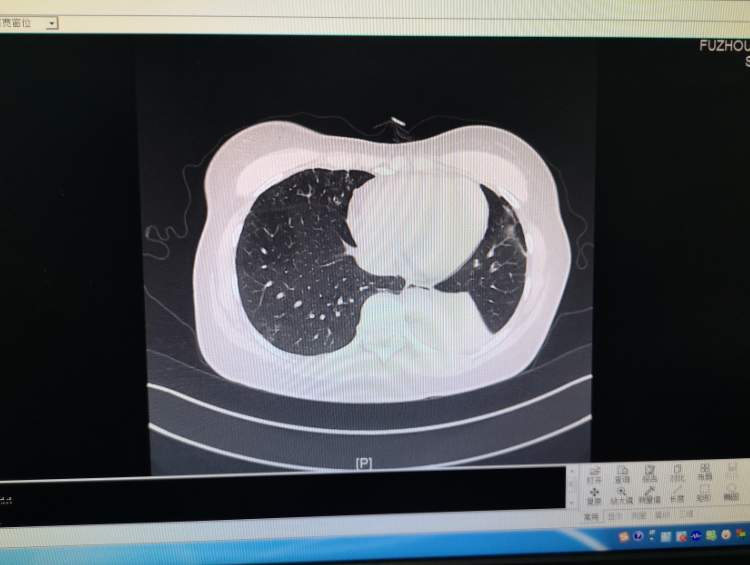

近日,福建省福州肺科医院接诊一名患者,该女子咳嗽两个月未愈,经查确诊为侵袭性支气管肺曲霉菌病。

医生表示,内镜检查时,发现患者肺部有非常严重的痰栓及坏死物,已经堵塞管腔,将坏死物活检后去做病理检查,发现了大量的霉菌。

专家表示,霉菌会依附在气管上,稍不注意就会造成气管黏膜的大出血。霉菌全年都有可能感染,尤其在天气潮湿的时候,特别容易生长。

目前,该女子通过抗霉菌治疗,情况日渐好转。